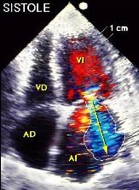

Ecocardiografía 2D. Marcada dilatación de las cavidades cardíacas.

Técnica doppler:

- Para valorar el flujo se utiliza el doppler color:

- Se detecta insuficiencia mitral, que suele ser ligera o moderada. No es la causa primaria de la miocardiopatía.

Doppler color